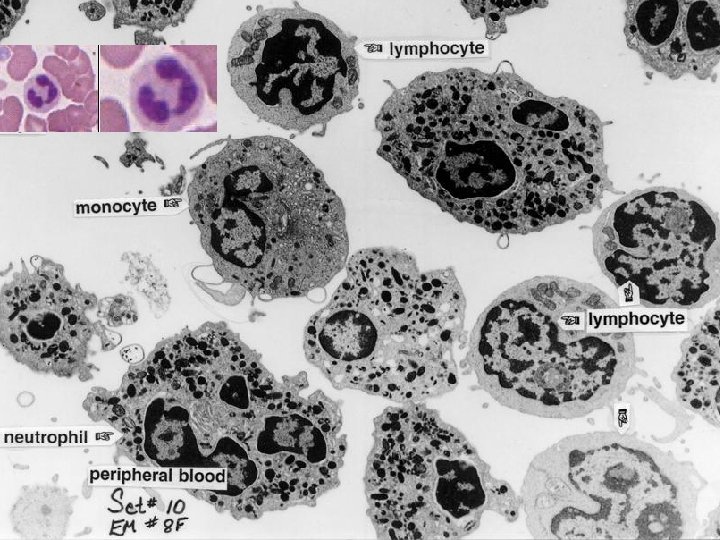

EM of white blood cells EM 8 f

Neutrophils Platelets Lymphocyte Monocyte Erythrocytes Slide 113

Study Questions % Prevalence in normal blood Distinguishing characteristics Contents of specific granules Life span 54 -62% 3 -5 connected lobes, cytoplasm is granulated 1. Azurophilic primary granules 1. Myeloperoxidase 2. Lysozyme 3. Defensins 2. Specific secondary granules 1 -4 days 25 -33% No granules in cytoplasm, densestaining nucleus surrounded by narrow cytoplasmic rim Agranular Hours to many years 3 -7% Largest agranular leukocyte with horshoe-shaped nucleus Agranular Hours to years 1 -3% Typically bilobed nucleus, cytoplasm has large eosinophilic granules 0 -0. 75% Cytoplasm contains dark blue or brown granules, basophilic nucleus normally obscured by dense cytoplasmic granules Neutrophils Lymphocytes Monocytes Eosinophils Basophils 1. Major basic proteins 2. Others 1. Heparin 2. Histamine 3. Others 1 -2 weeks Several months

White blood cells in blood